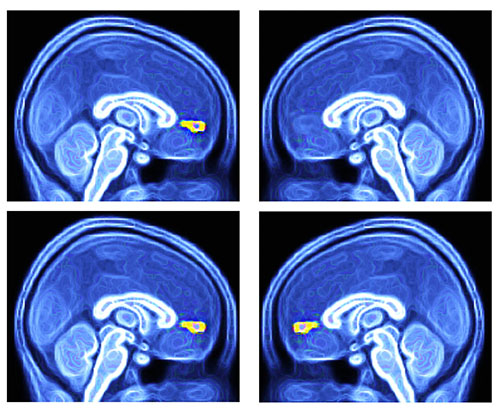

Photo at right:

(Top left) in ASD kids, VMPFC (yellow) activates normally to single presentation of favorite objects

(Top right) in ASD kids, VMPFC (missing yellow) does not activate normally to single presentation of favorite faces

(Bottom left and right) in TD kids, VMPFC (yellow) activates normally to single presentation of favorite faces and objects